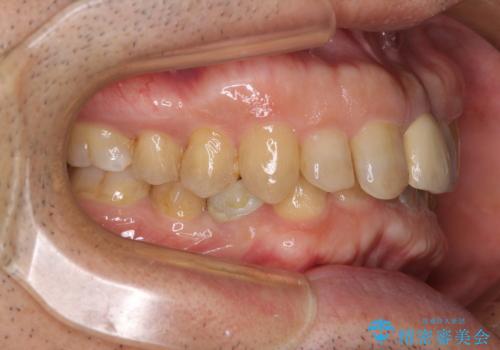

下顎は左右1本ずつ小臼歯が欠損しており、右側にはやや大きな欠損がありました。

欠損により下顎歯列は相対的に小さく、上顎に深く咬みこんでしまうディープバイトとなっていました。

咬合力が強く、インビザラインのみではディープバイトを改善することができず、半年間ほどワイヤー装置による矯正治療を行いました。

インプラントの埋入は矯正治療中に行い、矯正治療後はインプラント上補綴および、前歯のセラミック治療を行いました。